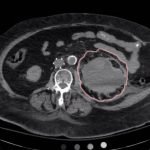

Bedside ultrasound was performed and demonstrated a hypoechoic area within the left kidney (images not shown). The non-contrast computed tomography (CT) of the abdomen and pelvis shows a significantly enlarged left kidney and a region of high-attenuation encapsulating the left kidney, concerning for acute hemorrhage.